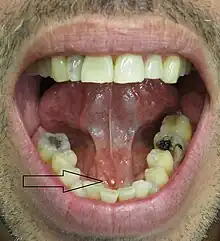

The stone seen in the submandibular duct on the person's right side

• Palpable hard lump, if the stone is located near the end of the duct.[1][3] If the stone is near the submandibular duct orifice, the lump may be felt under the tongue.